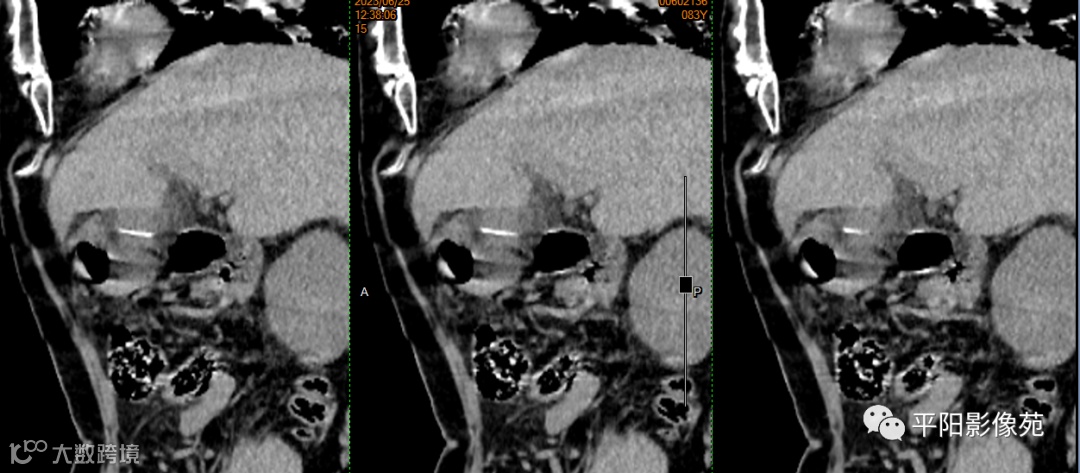

影像表现:

胃角胃壁增厚、毛糙,内侧可见一条状高密度,一端尖锐,周围可见软组织密度影包裹,边界不清。

于胃角处质硬组织行钝性+锐性分离,见其中包裹一长约5cm质硬骨刺,胃角处胃壁有破损,取出骨刺